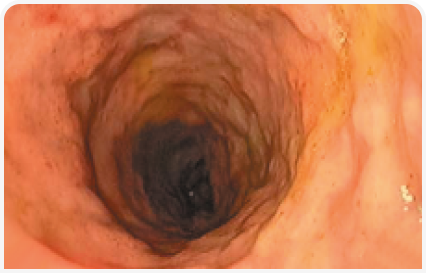

По результатам исследования образцов стенки желудка, полученных методом тонкоигольной аспирационной биопсии под контролем ультразвука, было обнаружено нейтрофильное воспаление. С учетом серьезных подозрений на наличие неоплазии было проведено эндоскопическое исследование желудка. При этом патологических изменений пищевода, дна желудка и большой кривизны обнаружено не было, однако малая кривизна и антральный отдел характеризовались ригидностью и не поддавались расширению при инсуфляции; язвенных поражений не обнаружили. Тяжесть поражений привратника делала невозможным прохождение эндоскопа через пилорус (Рисунок 8).

Гистопатологическое исследование показало наличие аденокарциномы желудка, при этом прогноз на исход заболевания был неблагоприятным, и через несколько дней животное подвергли эвтаназии (Вставка 3).